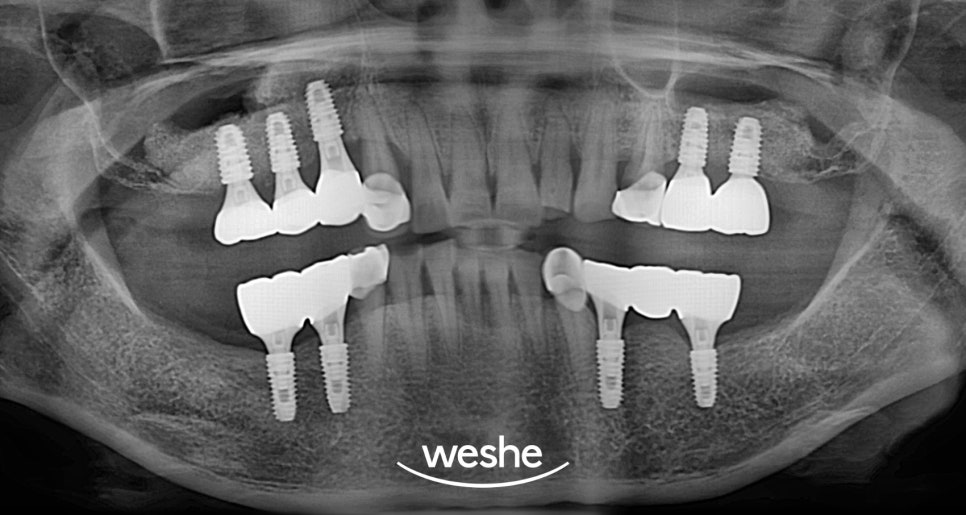

강서구 치과 에서 알려드리는

- 2차 수술 과 치료 완료 과정

2차는 1차보다

비교적 간단한 과정입니다.

상악동 거상과 함께 식립한

임플란트가 뼈와 잘 결합되었는지

확인한 후 지대주를 연결합니다.

이후 약 2-3주 정도의 치유 기간을

거쳐 최종 크라운을 제작합니다.

어금니 크라운은

저작력을 견딜 수 있도록

튼튼하게 제작해야 됩니다.

개인의 치아 색깔과 모양에 맞춰

치료 완료 후에는 정기적인

검진과 관리가 필요합니다.

상악동 거상술을 받은 부위는

일반적인 임플란트보다 더

세심한 관리가 필요할 수 있습니다.

통상적으로 6개월마다 정기검진을

받아 픽스처와 주변 조직의

상태를 확인해야 됩니다.

치료 기간 : 2025.01.10~2025.07.10